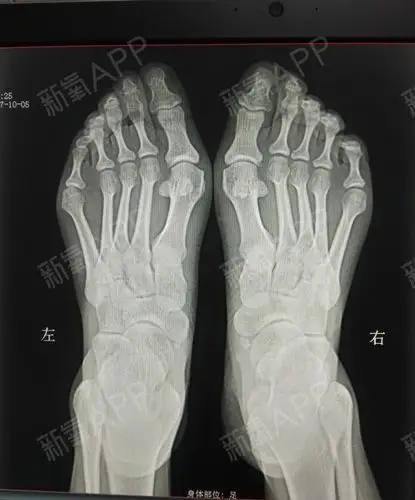

我脚的问题有点多,不仅有大脚骨,还有脚趾畸形,小脚_圈子-新氧美容